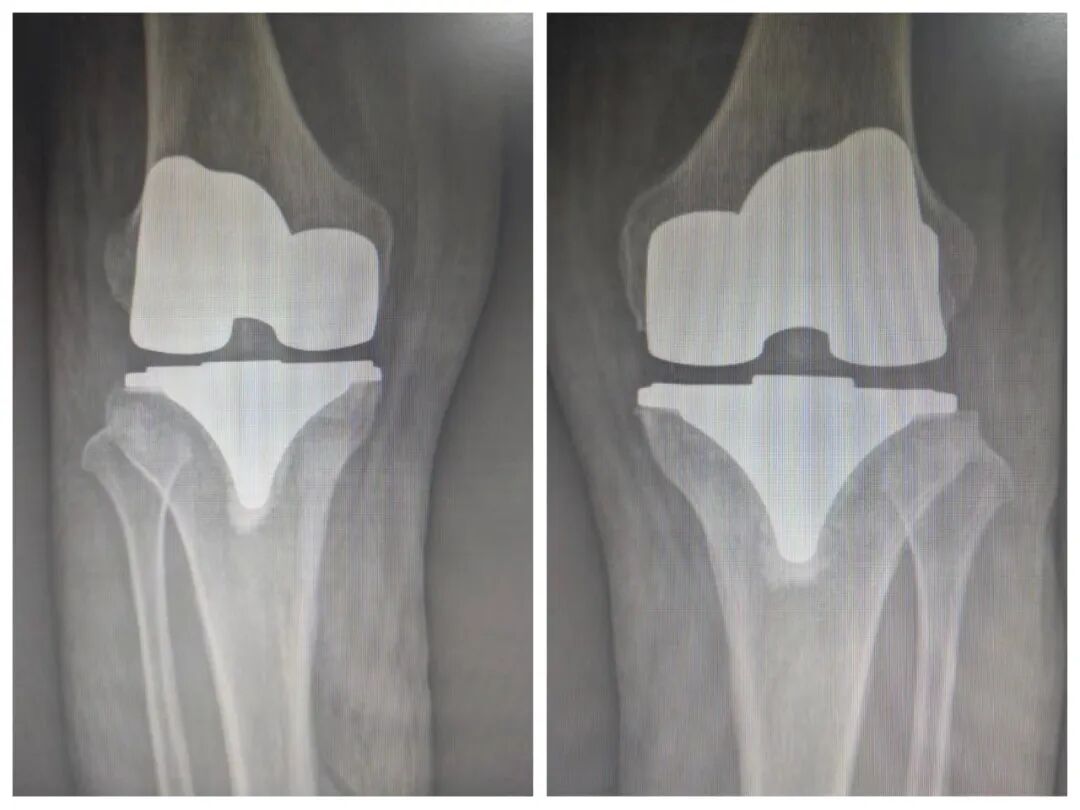

59岁刘某,以”双膝关节疼痛伴活动受限3年”主诉入院。入院诊断:双膝骨性关节炎;骨质疏松症。骨科鞠主任为患者行双膝人工关节表面置换术,其中使用骨科高值耗材费用从集采前的4.5万元左右,降到了集采后的9300元左右,患者在来院之前了解到需花费近5万余元,如今使用国家集采后的耗材,让患者家属对国家骨科耗材集采的好政策赞叹不已。

患者术前